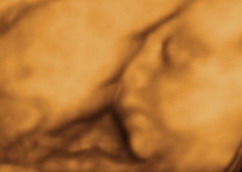

Az arcocskája tényleg meseszép!

Vickybabe: örülök, hogy Levente is csodaszép!!! De jó, hogy így kikerekedik a kis pofijuk erre az időre, már nagyon várom a hétfőt, hogy láthassam Kiscicámat!